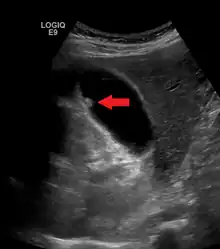

| A polyp in the gall bladder as seen on ultrasound |

Diagnosis is typically by ultrasound or CT imaging.

Ultrasound image of gallbladder polyps measuring 3–7 mm.